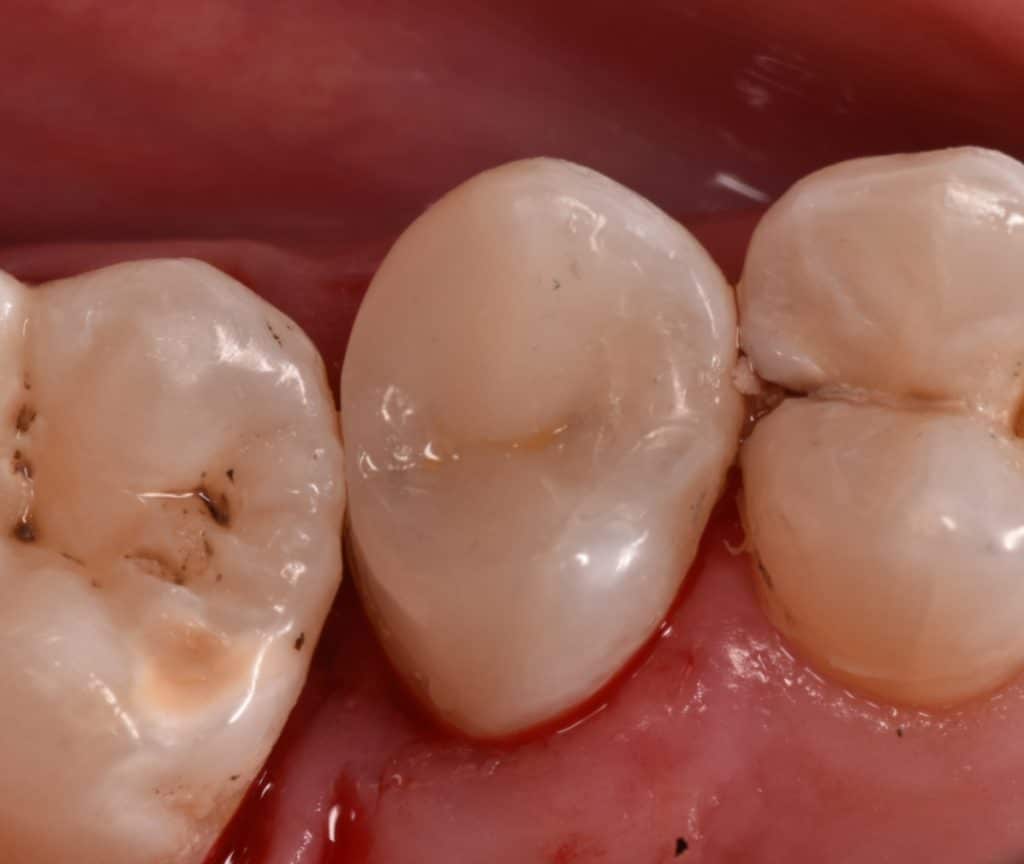

Ever x posterior for dentin replacement , strengthen the filling and can stop cracks

Immediate result

Palatal view

Immediate after rubber dam removal